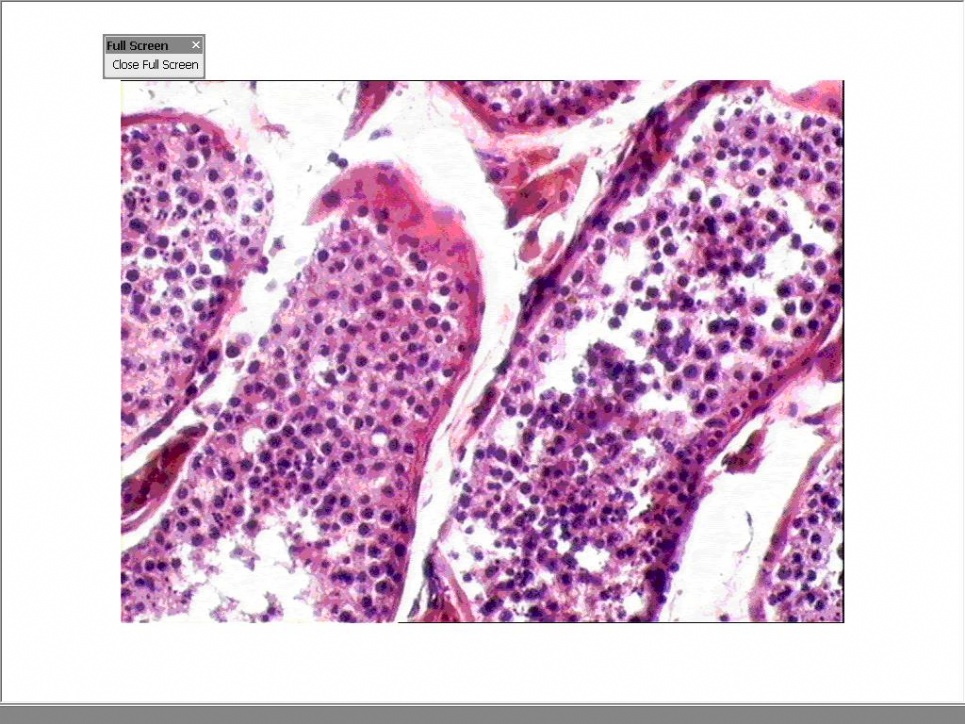

精巢切片

精巢切片,卵巢切片

睾丸:产生精子,分泌雄性激素.